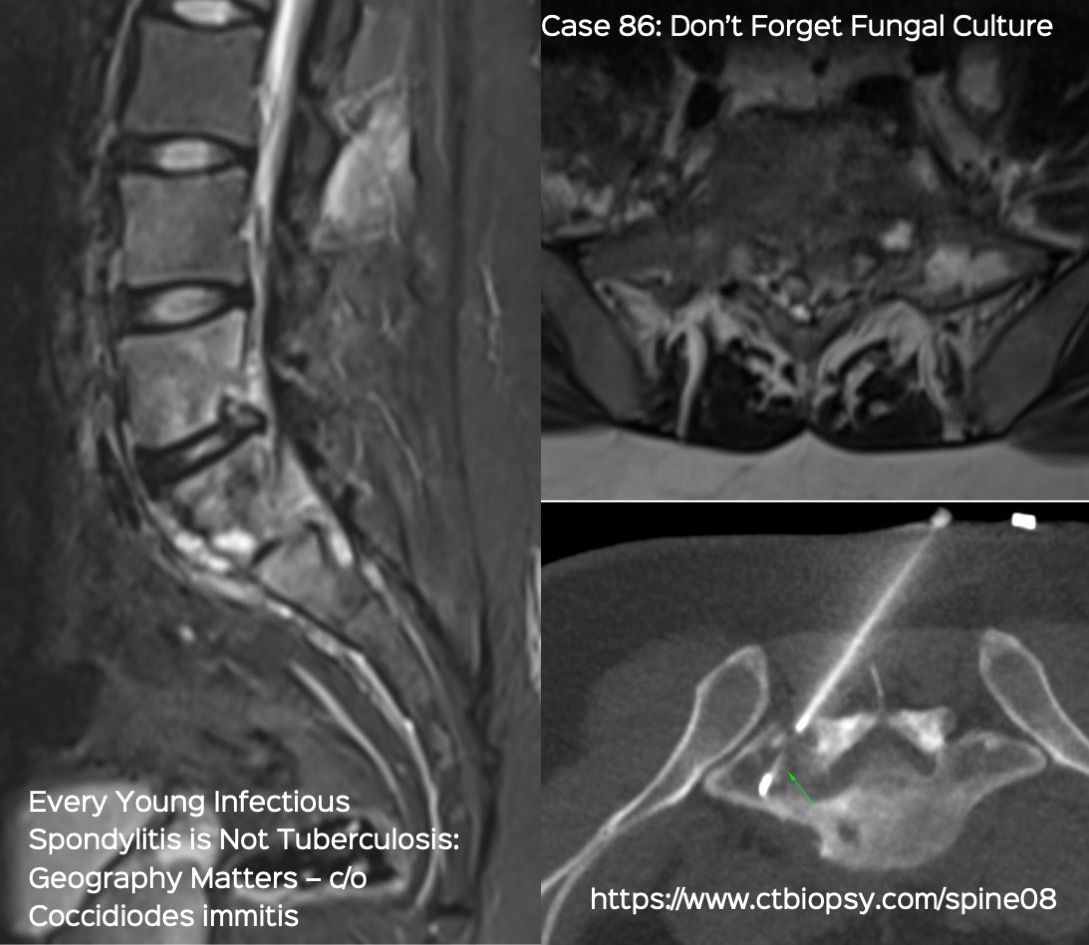

Case 86: Every Young Infectious Spondylitis is not Tuberculosis: Geography Matters

Bhavin Jankharia - 02 April 2022